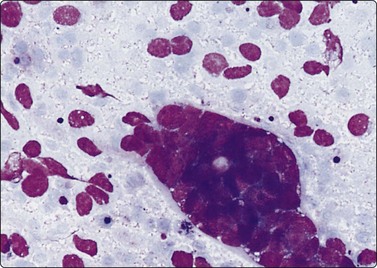

Fig. 12.3 Renal cyst macrophages

Clustered atypical-looking macrophages in fluid aspirated from a simple renal cyst (MGG, HP).